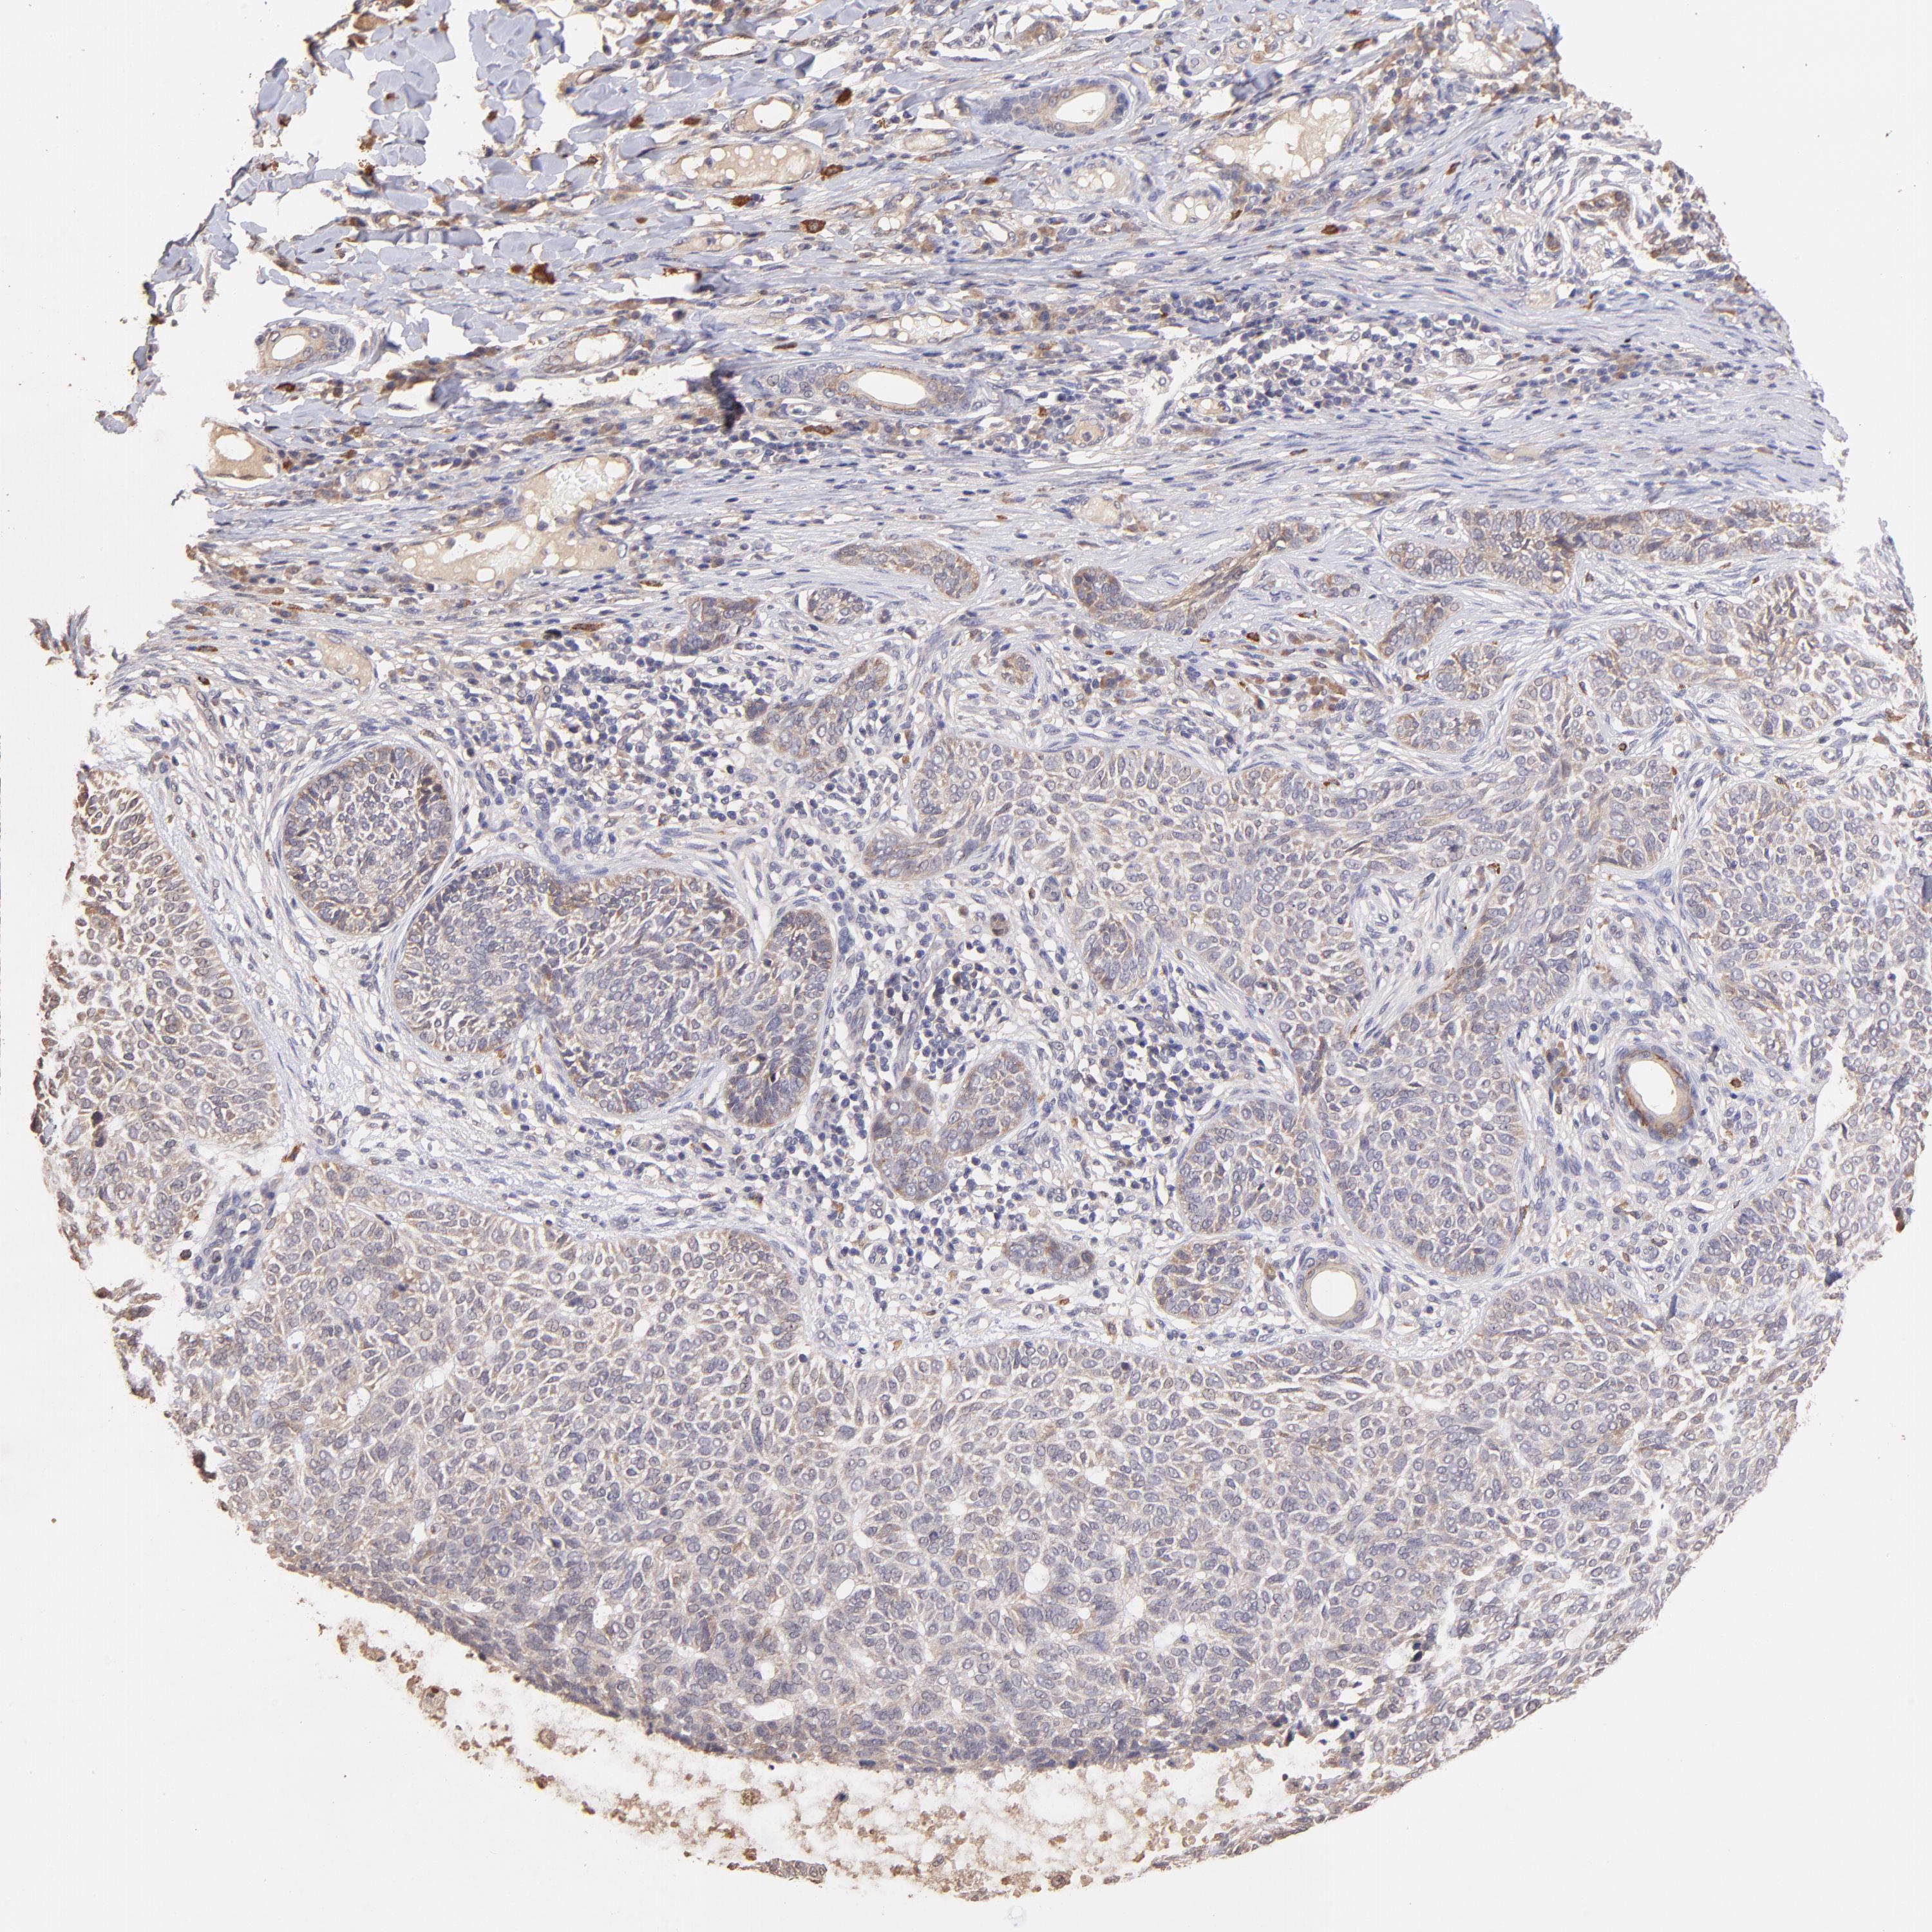

SKIN CANCER - Protein expressioni

A mouse-over function shows sample information and annotation data. Click on an image to view it in a full screen mode. Samples can be filtered based on level of antibody staining by selecting one or several of the following categories: high, medium, low and not detected. The assay and annotation is described here.

Antibody staining in the annotated cell types in the current human tissue is reported as not detected, low, medium, or high, based on conventional immunohistochemistry profiling in selected tissues. This score is based on the combination of the staining intensity and fraction of stained cells.

Each image is clickable and will lead to virtual microscopy that enables deeper exploration of all samples and also displays staining intensity scores, fraction scores and subcellular localization as well as patient and tissue information for each sample.

Antibody HPA002633

Antibody HPA046758

Antibody CAB010906

Squamous cell carcinoma, NOS

Basal cell carcinoma